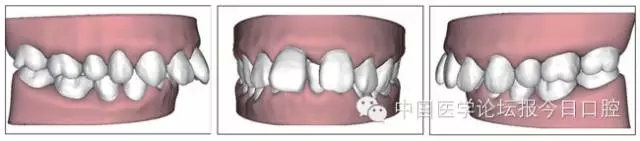

X線檢查

全口曲面體層片(圖3)顯示,患者全牙列牙槽骨吸收;根尖片(圖4)示11近中牙槽骨角形吸收已達(dá)根尖1/3,21牙槽骨嵴頂吸收至根1/2,23牙槽骨近中骨板角形吸收至根1/2。磨牙區(qū)骨嵴頂吸收3mm。治療前頭顱側(cè)位片見(jiàn)圖3,治療前ODS模型見(jiàn)圖5。

16.webp.jpg

17.webp.jpg

圖11 治療后ODS模型